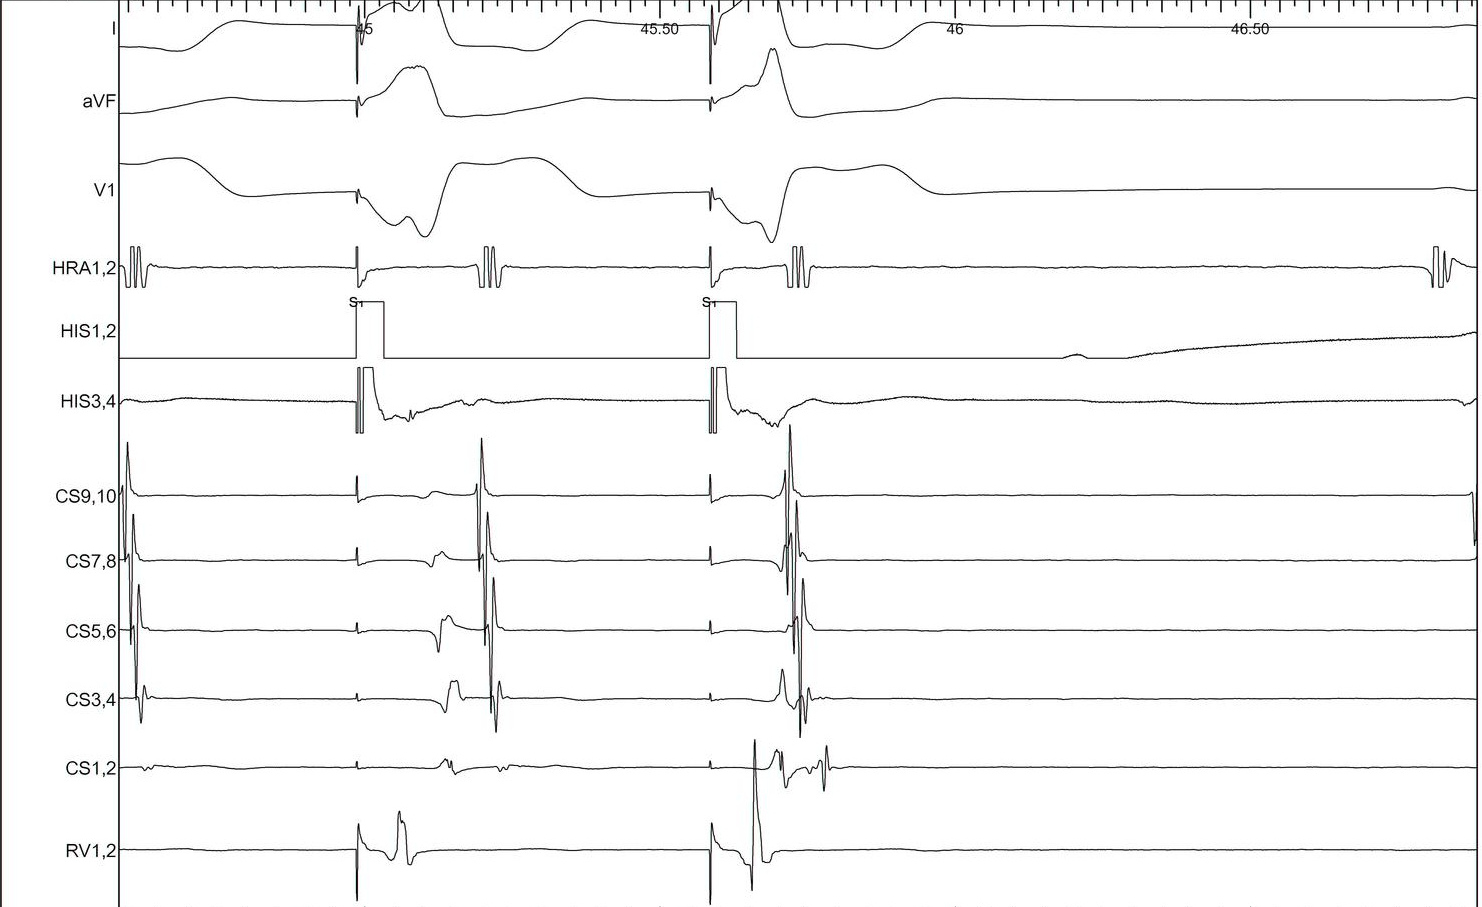

Bundle branch block

lbbb_narrow.jpg

lbbb_narrow_measurements.jpg

coumel.jpg